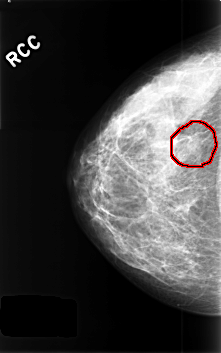

C_0437_1.RIGHT_CC

RIGHT_CC LINES 4584 PIXELS_PER_LINE 2864 BITS_PER_PIXEL 12 RESOLUTION 50 OVERLAY

FILE: C_0437_1.RIGHT_CC.OVERLAY

TOTAL_ABNORMALITIES 1

ABNORMALITY 1

LESION_TYPE MASS SHAPE FOCAL_ASYMMETRIC_DENSITY MARGINS N/A

ASSESSMENT 3

SUBTLETY 3

PATHOLOGY BENIGN_WITHOUT_CALLBACK

TOTAL_OUTLINES 1

BOUNDARY